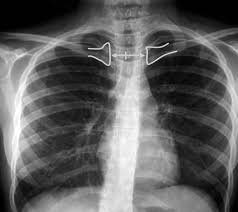

Desde un punto de vista anatómico y geométrico, las clavículas son estructuras óseas horizontales que se proyectan anteriormente y que, en condiciones ideales de alineación, deben aparecer equidistantes de las apófisis espinosas de las vértebras torácicas. La columna dorsal, al situarse en el plano medio sagital del cuerpo, constituye una referencia central estable. Cuando el paciente está correctamente posicionado sin rotación, las apófisis espinosas se observan centradas entre los extremos mediales de ambas clavículas. Esta simetría refleja que el plano coronal del tórax es paralelo al receptor de imagen y perpendicular al haz de rayos X.

Si el paciente gira su tronco hacia un lado, aunque sea de manera leve, se produce una modificación en la distancia relativa entre cada clavícula y la línea media vertebral. La clavícula del lado hacia el cual rota el paciente se proyectará más cercana a la columna, mientras que la contralateral parecerá más alejada. Este fenómeno obedece a principios básicos de proyección geométrica: las estructuras que se aproximan al receptor de imagen se visualizan con menor magnificación, mientras que aquellas que se alejan experimentan mayor magnificación y desplazamiento aparente. La rotación genera, por tanto, una asimetría cuantificable que puede evaluarse comparando visualmente la distancia entre las extremidades mediales claviculares y las apófisis espinosas.

Es importante destacar que esta relación geométrica se mantiene independientemente de si el paciente está de frente al tubo de rayos X o al chasis en el momento de la exposición. Ello se debe a que la referencia utilizada no depende de la orientación anteroposterior o posteroanterior, sino de la simetría interna del esqueleto axial respecto al plano medio. Aunque cambie la dirección del haz, la columna dorsal continúa representando el eje central del cuerpo, y las clavículas conservan su disposición bilateral. Por consiguiente, la evaluación de su relación mutua sigue siendo válida como indicador de rotación en cualquiera de estas proyecciones.